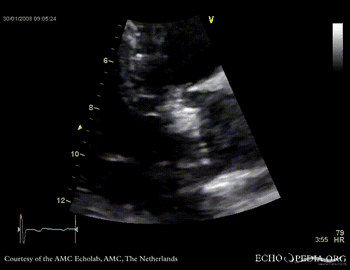

Aortic valve stenosis

AoS17